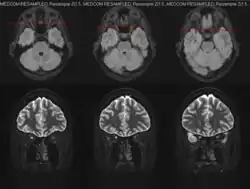

Magnetic resonance imaging (MRI) is a robust and sensitive diagnostic modality for the detection of optic neuritis. Imaging of the optic nerve with MRI shows increased signal on the affected side. There is contrast enhancement of the symptomatic optic nerve and sheaths acutely or intrinsic signal increase (looking brighter) within ≥ 3 months. One study found that MRI of the orbits with fat suppression and gadolinium enhancement detected acute optic neuritis lesions in 95% of affected individuals within 20 days of vision loss.[23] Another study found that T2-weighted images with fat suppression and short tau inversion recovery (STIR) detected lesions in up to 89% of acute optic neuritis cases with abnormalities persisting for as long as 6 weeks in 92% of cases.[24]

Magnetic Resonnance Imaging (MRI) during an episode of optic neuritis.

Identification of optic nerve, orbital, brain, and meningeal involvement with MRI can also help to better characterize the underlying cause of optic neuritis upon initial evaluation. Unilateral optic nerve involvement is more common MS while bilateral optic nerve involvement is more common in NMOSD and MOGAD.[7] T2-hyperintense and gadolinium-enhancing lesions in multiple regions of the brain and/or spinal cord may be highly suggestive or diagnostic of MS. Such lesions found in the periependymal, fornix, and hypothalamic lesions may be more suggestive of NMOSD.[7] Involvement of the optic chiasm or optic tract are more suggestive of NMOSD-optic neuritis; involvement of the retrobulbar optic nerve can be seen in both NMOSD and MOGAD, but more commonly in MOGAD; perineural optic nerve involvement is often suggestive of MOGAD-optic neuritis, but should not preclude the investigation of other autoimmune or infectious etiologies.[7]